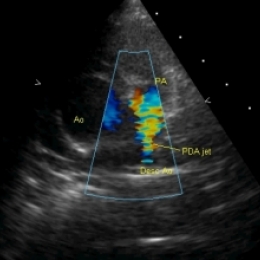

Эхокардиография (Эхо-КГ) — это безболезненное обследование сердца при помощи ультразвука, оно позволяет увидеть строение и работу сердца вашего ребёнка. Прибор выводит изображение на экран, как и при УЗИ органов брюшной полости или малого таза, затем делается несколько снимков и пишется заключение врача УЗ-диагностики. При помощи этого обследования можно обнаружить открытый Баталов проток и оценить изменения, которые могут возникнуть сердце при данном пороке (увеличение камер сердца, при отсутствии лечения основного заболевания, как правило, приводящее к сердечной недостаточности).